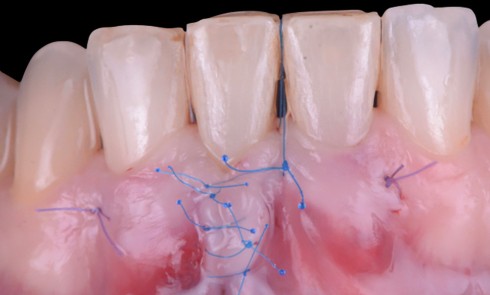

Notre choix s’est porté sur une intervention chirurgicale parodontale la moins invasive possible, en utilisant une gouttière thermoformée souple. Cette approche a permis l’amélioration objective de l’esthétique du sourire de la patiente.